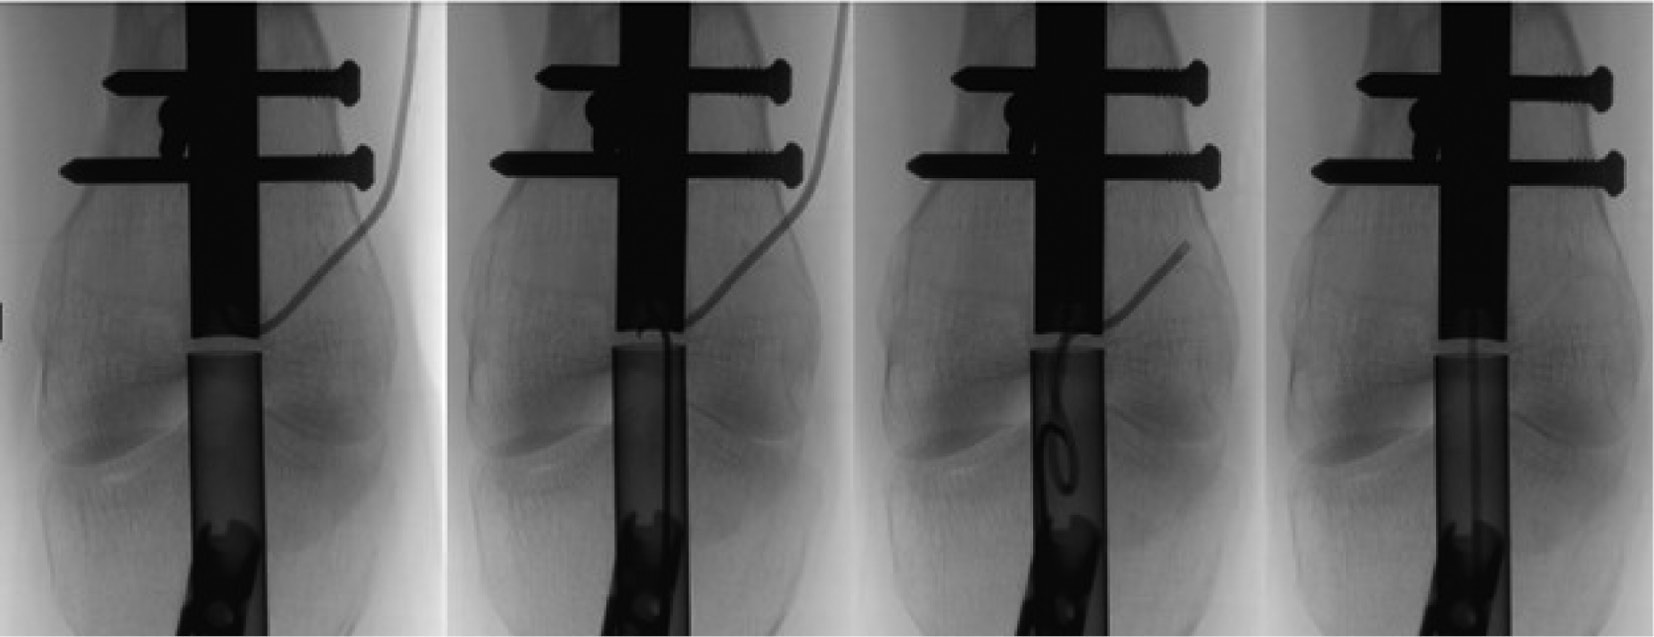

4. Once one of the distal screws/pegs is removed, the nail insertion incision is re-opened and a 3.2 mm K-wire is placed through the patella tendon (Figure 23). It is important that the guidewire is aligned perfectly to the center of the nail under fluoroscopy in both the coronal and sagittal planes (Figure 24). The K-wire can be tapped in using a mallet (Figure 25). It is helpful to have the fluoroscope in the AP plane aligned orthogonal to the limb (Figure 26).

5. An incision along the K-wire through the patella tendon is performed (Figure 27). The 12 mm cannulated cone is inserted over the K-wire through the patella tendon to the femoral notch (Figures 28 and 29). The hitting device for cone insertion (Figure 30) is used to place the cone’s thick part close to the bone (Figure 31). The 13/12 medium size tube is inserted over the cone through the joint and fixed in place by using a 12 mm hitting device (Figure 32). Tap the hitting device until it sits tight in the bone, but make sure it is not contacting the cable (Figure 33). The hitting device and cone are now removed, leaving the K-wire in place (Figure 34). The tube remains inserted in the bone to ensure clear passage and prevent any debris from passing into the knee joint during nail removal. The 12 mm straight motorized nail reamer is used to open a canal to the nail (Figure 35). The reamer is run until it just begins to contact the cable (Figure 36). The reamer and K-wire are now removed leaving the tube in place.

Figure 23. Once one of the distal screws/pegs is removed, the nail insertion incision is re-opened and a 3.2 mm K-wire is placed through the patella tendon.

jposna20220031_fig23.jpg

Figure 24. It is important that the guidewire is aligned perfectly to the center of the nail under fluoroscopy in both the coronal and sagittal planes.

jposna20220031_fig24.jpg

Figure 25. Tap the K-wire into the distal end of the nail with a mallet.

jposna20220031_fig25.jpg

Figure 26. It is helpful to have the fluoroscope oriented perpendicular to the plane of the distal femur.

jposna20220031_fig26.jpg